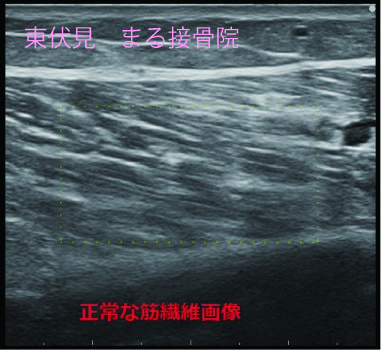

下のエコー画像、ふくらはぎの筋腹内に断裂部分(空洞部分)が診られ、特殊な撮影方法で出血度合も確認できます。

エコー検査は筋肉の状態を正確に確認でき、的確に治療をできます。